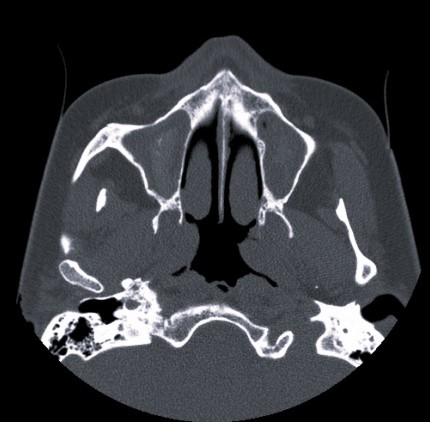

Полипозный этмоидит

Полипозный этмоидит 110 фото